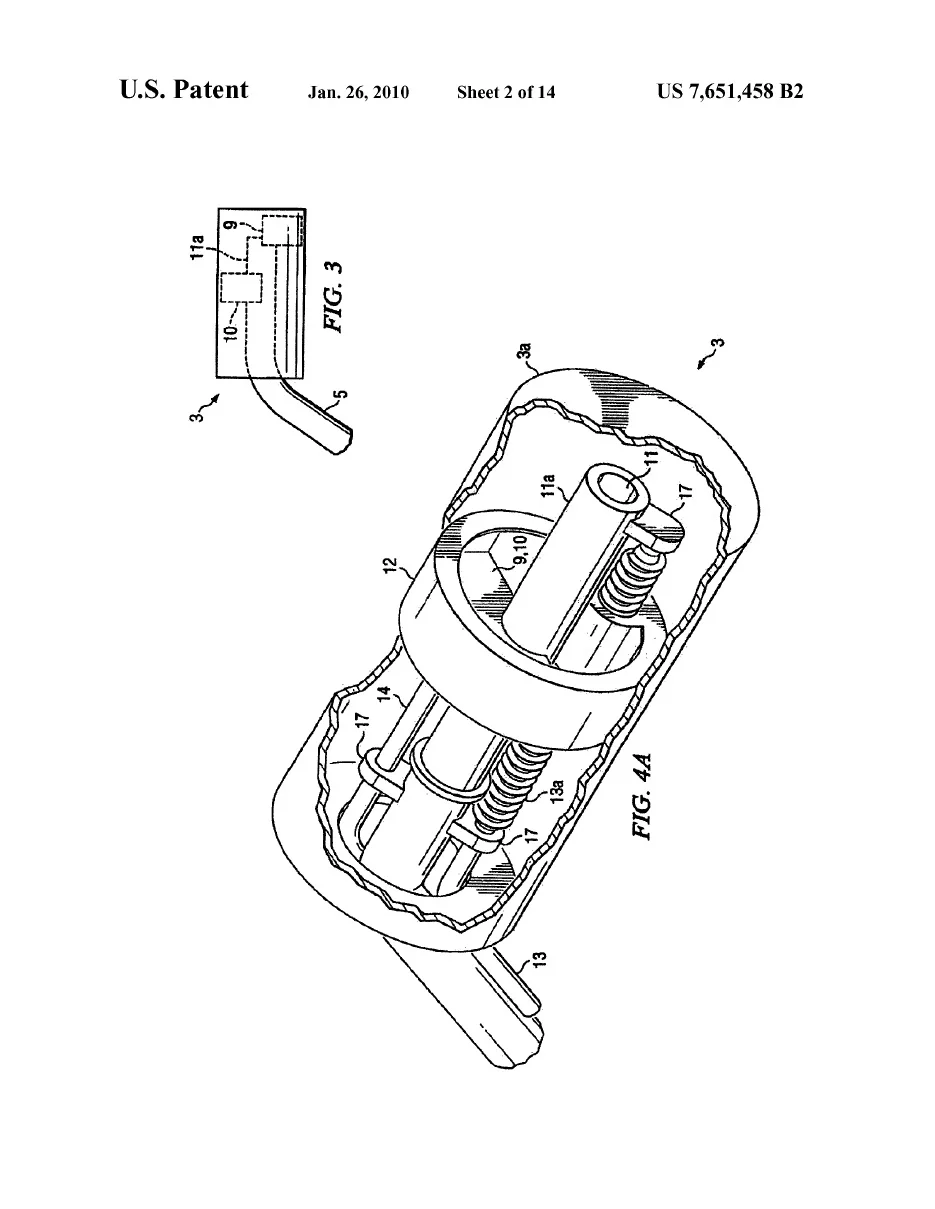

Angioplasty Balloon Inflator

Schnieder-Namic Inc (boston Scientific)

Designed patented angioplasty balloon inflator with a novel mechanism for controlling balloon pressure. Designed for Schnieder-Namic Inc which later became part of Boston Scientific. Received patent for mechanism and ergonomics of the handheld surgical device.

Intracavitary Brachytherapy Applicator

nucletron bv

Designed and developed innovative medical devices for radiation oncology. Our team included myself, a radiation oncologist, a radiation physicist, and a chemist. The project shown above is the “Adaptive Intracavitary Brachytherapy Applicator” for the treatment of cervical cancer. Received a patent for its internal mechanism which allows the radiation shielding to be adjusted for each patient. The device was licensed by a multinational medical device company based in the Netherlands (Nucletron BV). Patent #7651458, “Adaptive Intercavitary Brachytherapy Applicator”.